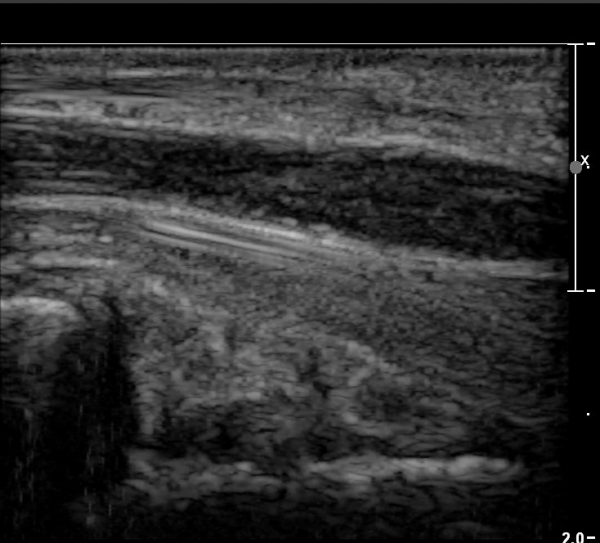

Á¤Á߽Űæ Á¾´Ü¸é°Ë»ç¿¡¼­µµ ¼Õ¸ñ ¸»´ÜºÎ¿¡¼­ ¼ö±Ù°ü ±ÙÀ§ºÎ±îÁö À̾îÁø Àú¿¡ÄÚ

Á¾¾çÀÌ °üÂûµÊ(»çÁø 8, 9, 10, 11).

Á¾¾ç¿¡ ÀÇÇÑ Á¤Á߽Ű渻´Ü°¡ÁöÀÇ ¾Ð¹ÚÀÌ ÃßÁ¤µÇ¾úÀ¸³ª  ÃÊÀ½ÆÄ°Ë»ç»ó ¼Õ¸ñºÎÀ§¿¡¼­ Á¤Á߽Ű泻

Àú¿¡ÄÚ Á¾¾çÀÌ °üÂûµÇ°í Àú¿¡ÄÚ Á¾¾çÀÇ ½Å°æ³» À§Ä¡°¡ Âü°í¹®Çå¿¡¼­ º¸°íÇÑ ¹Ù¿Í °°ÀÌ

Á¤Á߽Ű泻¿¡¼­ µÎµ¢±ÙÀ°À» Áö¹èÇÏ´Â ¿îµ¿½Å°æÀÇ À§Ä¡¿Í ÀÏÄ¡ÇÏ¿© Á¤Á߽ŰæÁß¿¡¼­ µÎµ¢±ÙÀ°À»

Áö¹èÇÏ´Â ½Å°æ µ¢¾î¸®(fascicle)ÀÇ ½Å°æÁ¾À¸·Î ÃßÁ¤ÀÌ °¡´ÉÇϸç ÀÓ»óÀû ¼Ò°ß°úµµ ÀÏÄ¡ÇÑ´Ù.